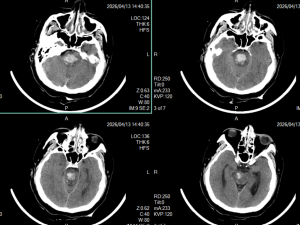

2026年4月29日 Home立体定向技术脑干出血急诊穿刺引流,抢救生命 脑干出血急诊穿刺引流,抢救生命 By admin 立体定向技术 0 Comments 病人1,4月13日急性脑干出血,迅速神志不清 术前CT显示脑干出血 脑干出血发病时 手术计划 术后复查,显示定位准确,穿刺道完全符合术前计划 术后7天,血肿基本引流干净 手术后15天情况 现病人生命体征平稳,正在促醒康复中 About Author admin Add a Comment 取消回复您的邮箱地址不会被公开。 必填项已用 * 标注Comment:*Name:* Email Address:* Website: Save my name, email, and website in this browser for the next time I comment. Δ